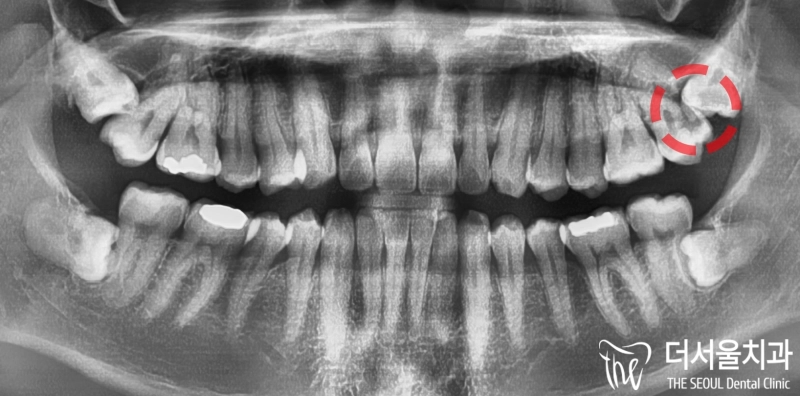

안녕하십니까, 더서울 문정동치과 쌍둥이 박현성 원장입니다. 사랑니라는 치아가 생겼을때, 의료진들은 되도록 빠른 시일 내에 빼는 것이 좋다 그렇게 알려드리고

우리가 흔히 말하는 사랑니 는 맨 뒤에 있는 큰 어금니로 전문용어로 ‘제3대구치’라고 부르고 있습니다. 사실 관리만 잘하면 치아를 뽑지